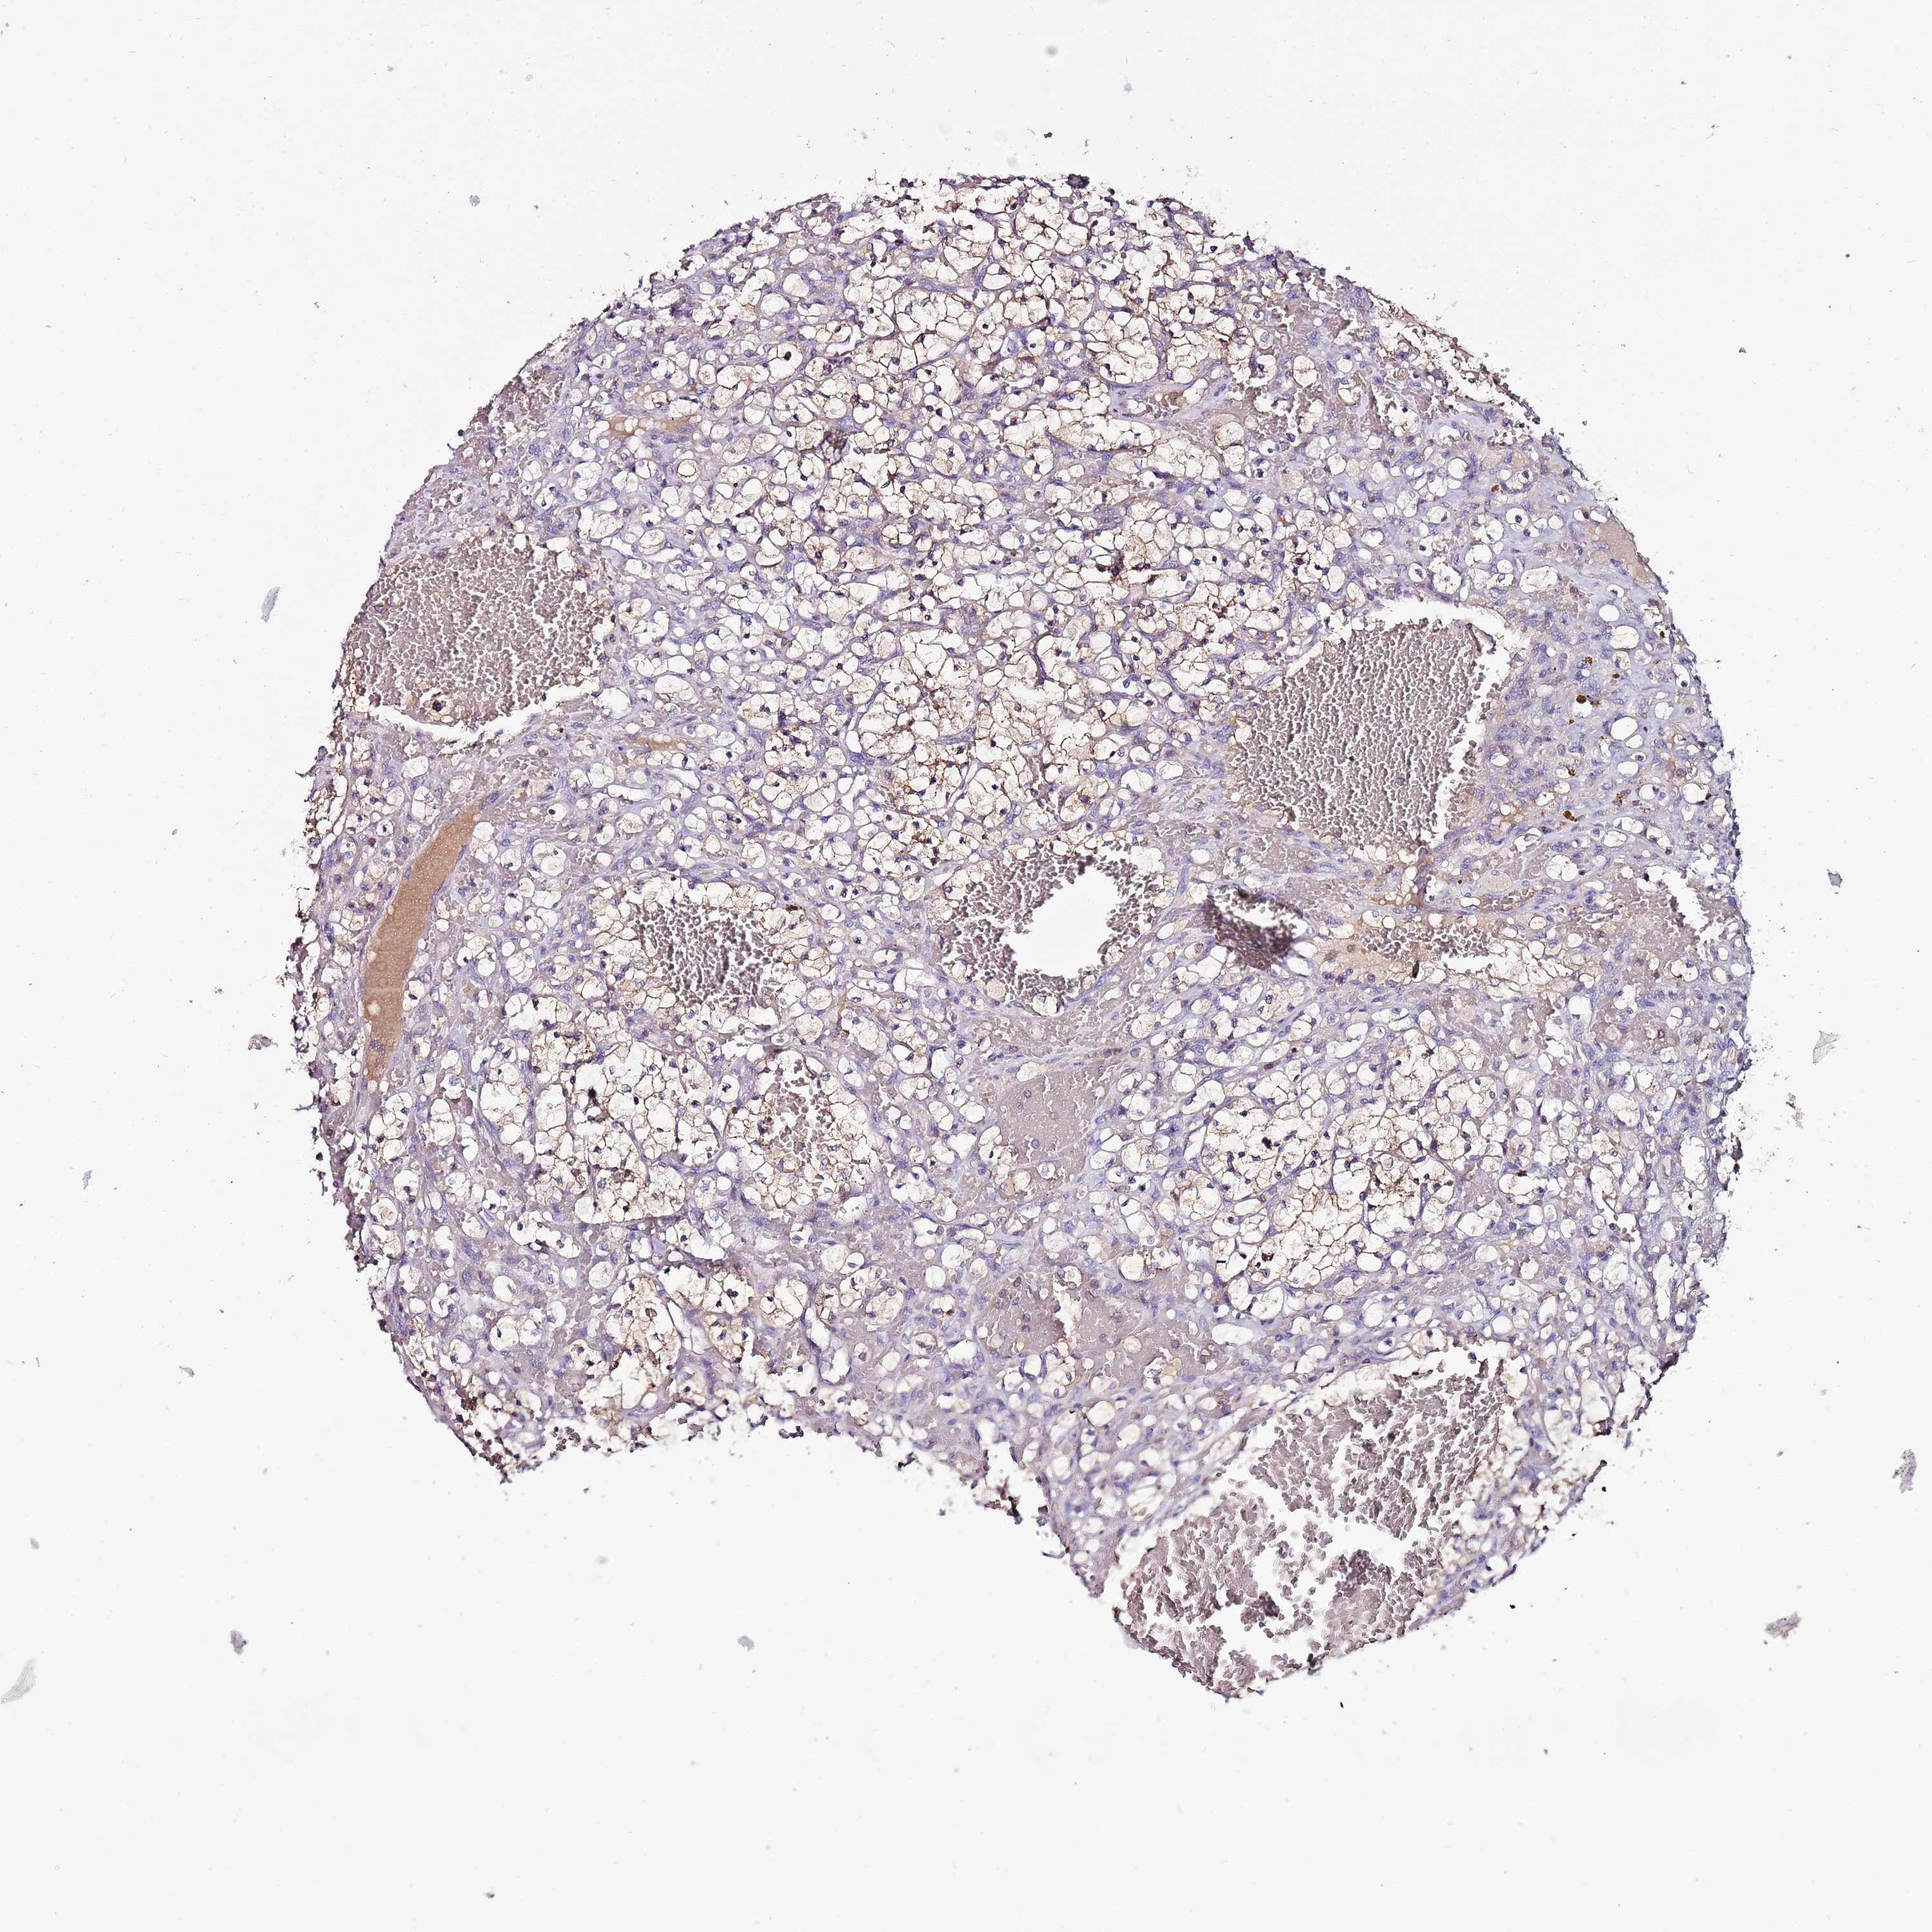

KIDNEY RENAL PAPILLARY CELL CARCINOMA (TCGA) - Interactive survival scatter ploti

The Survival Scatter plot shows the clinical status (i.e. dead or alive) for all individuals in the patient cohort, based on the same data that underlies the corresponding Kaplan-Meier plots. Patients that are alive at last time for follow-up are shown in blue and patients who have died during the study are shown in red.

The x-axis shows the expression levels (FPKM) of the investigated gene in the tumor tissue at the time of diagnosis. The y-axis shows the follow-up time after diagnosis (years). Both axes are complimented with kernel density curves demonstrating the data density over the axes. The top density plot shows the expression levels (FPKM) distribution among dead (red) and alive patients (blue). The right density plot shows the data density of the survived years of dead patients with high and low expression levels respectively, stratified using the cutoff indicated by the vertical dashed line through the Survival Scatter plot. This cutoff is automatically defined based on the FPKM cutoff that minimizes the p-score. The cutoff can be changed by dragging the vertical line or by entering a cutoff value in the square labeled "Current cut-off".

Under the Survival Scatter plot the p-score landscape (black curve; left axis) is shown together with dead median separation (red curve; right axis). Dead median separation is the difference in median mRNA expression between patients who have died with high and low expression, respectively. It is calculated as follows: median FPKM expression of dead patients with high expression - median FPKM expression of dead patients with low expression. This is intended to aid the user in visually exploring custom cutoffs and the associated p-scores and dead median separation.

Individual patient data is displayed and can be filtered by clicking on one or more of the category buttons on the top of the page. Categories describing expression level and patient information include: high, low, alive, dead, female, male and tumor stages. The scale of the x-axis can be toggled between linear and log-scale by clicking on the "x log" button. Mouse-over function shows TCGA ID, patient information and mRNA expression (FPKM) for each patient.

& Survival analysisi

Kaplan-Meier plots summarize results from analysis of correlation between mRNA expression level and patient survival. Patients were divided based on level of expression into one of the two groups "low" (under cut off) or "high" (over cut off). X-axis shows time for survival (years) and y-axis shows the probability of survival, where 1.0 corresponds to 100 percent.

IGIP is potential prognostic, high expression is favorable in Kidney Renal Papillary Cell Carcinoma (TCGA)